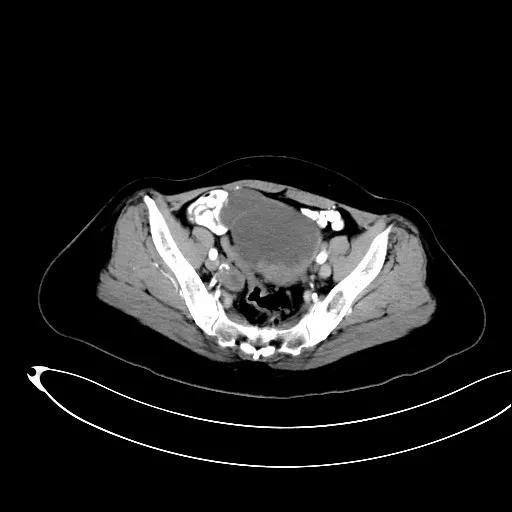

某患者因为“腹痛1周”而入院,外院B超提示子宫上方囊实性肿物,CT提示:左侧附件区占位,并盆腔及腹主动脉旁淋巴结转移。右肾动脉有右肾动脉及异位右肾动脉,其下均有肿大淋巴结。

妇科一病区严格遵循指南推荐,在影像学或探查淋巴结阳性的晚期卵巢癌中,若能达到满意减瘤,仍常规行盆腔及腹主动脉旁肿大淋巴结切除/清扫术(如下图举例)。通过前期初步统计分析,肠系膜下动脉至肾静脉下淋巴结转移阳性率为25%左右,在全部腹主动脉旁淋巴结转移患者中约占30%,显示了肾静脉下腹主动脉旁淋巴结清扫的价值。其对生存的影响有待进一步观察。